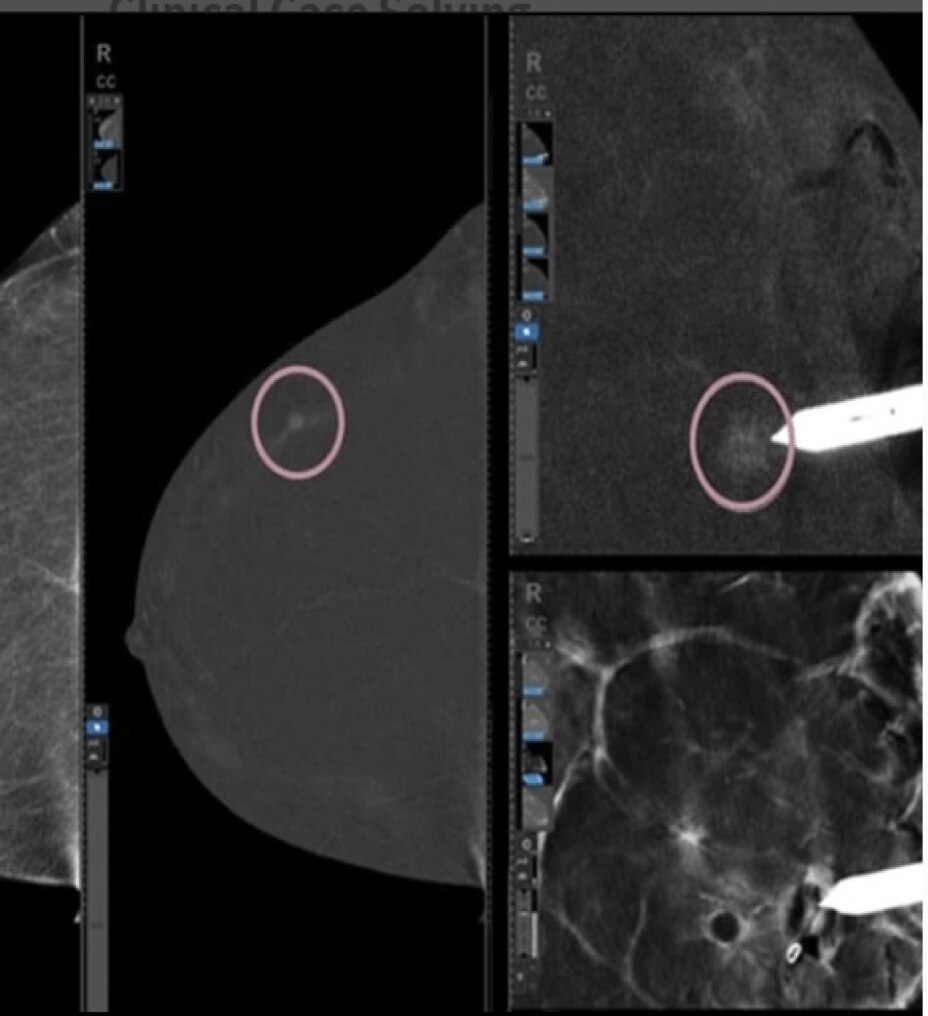

Calidad de imagen excepcional y exámenes cómodos para el paciente con SIGNA Voyager Premier Edition